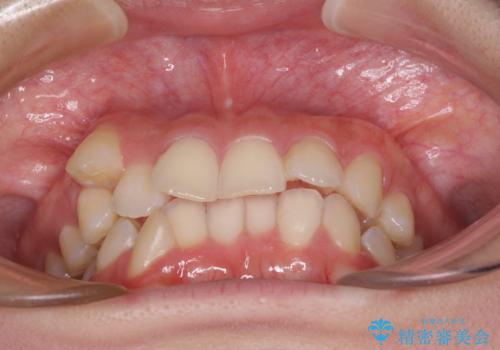

- 八重歯と上顎正中のズレを気にして来院された患者様です。

インビザラインによる矯正治療を希望されたため、八重歯改善のための抜歯矯正部分や上顎正中の大幅に位置移動は、補助装置やワイヤー矯正を併用し、その後はインビザラインにて行うこととしました。

骨格的に下顎が左側に変位していたため、上下正中を合わせることは困難であることは分かっていましたが、可能な限り合わせることができました。